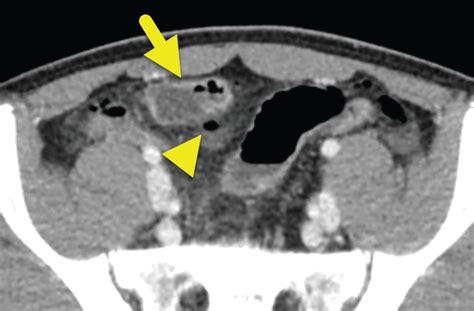

CT Scan Structural imaging of the abdomen Moderate (good for complications like obstruction)

The interpretation of a Meckel’s Diverticulum Scan requires expertise in nuclear medicine. A positive result is indicated by a “hot spot”—an area of increased radioactivity that appears in the lower abdomen during the imaging sequence. This “hot spot” corresponds to the area where the technetium-99m has accumulated in the gastric mucosa.